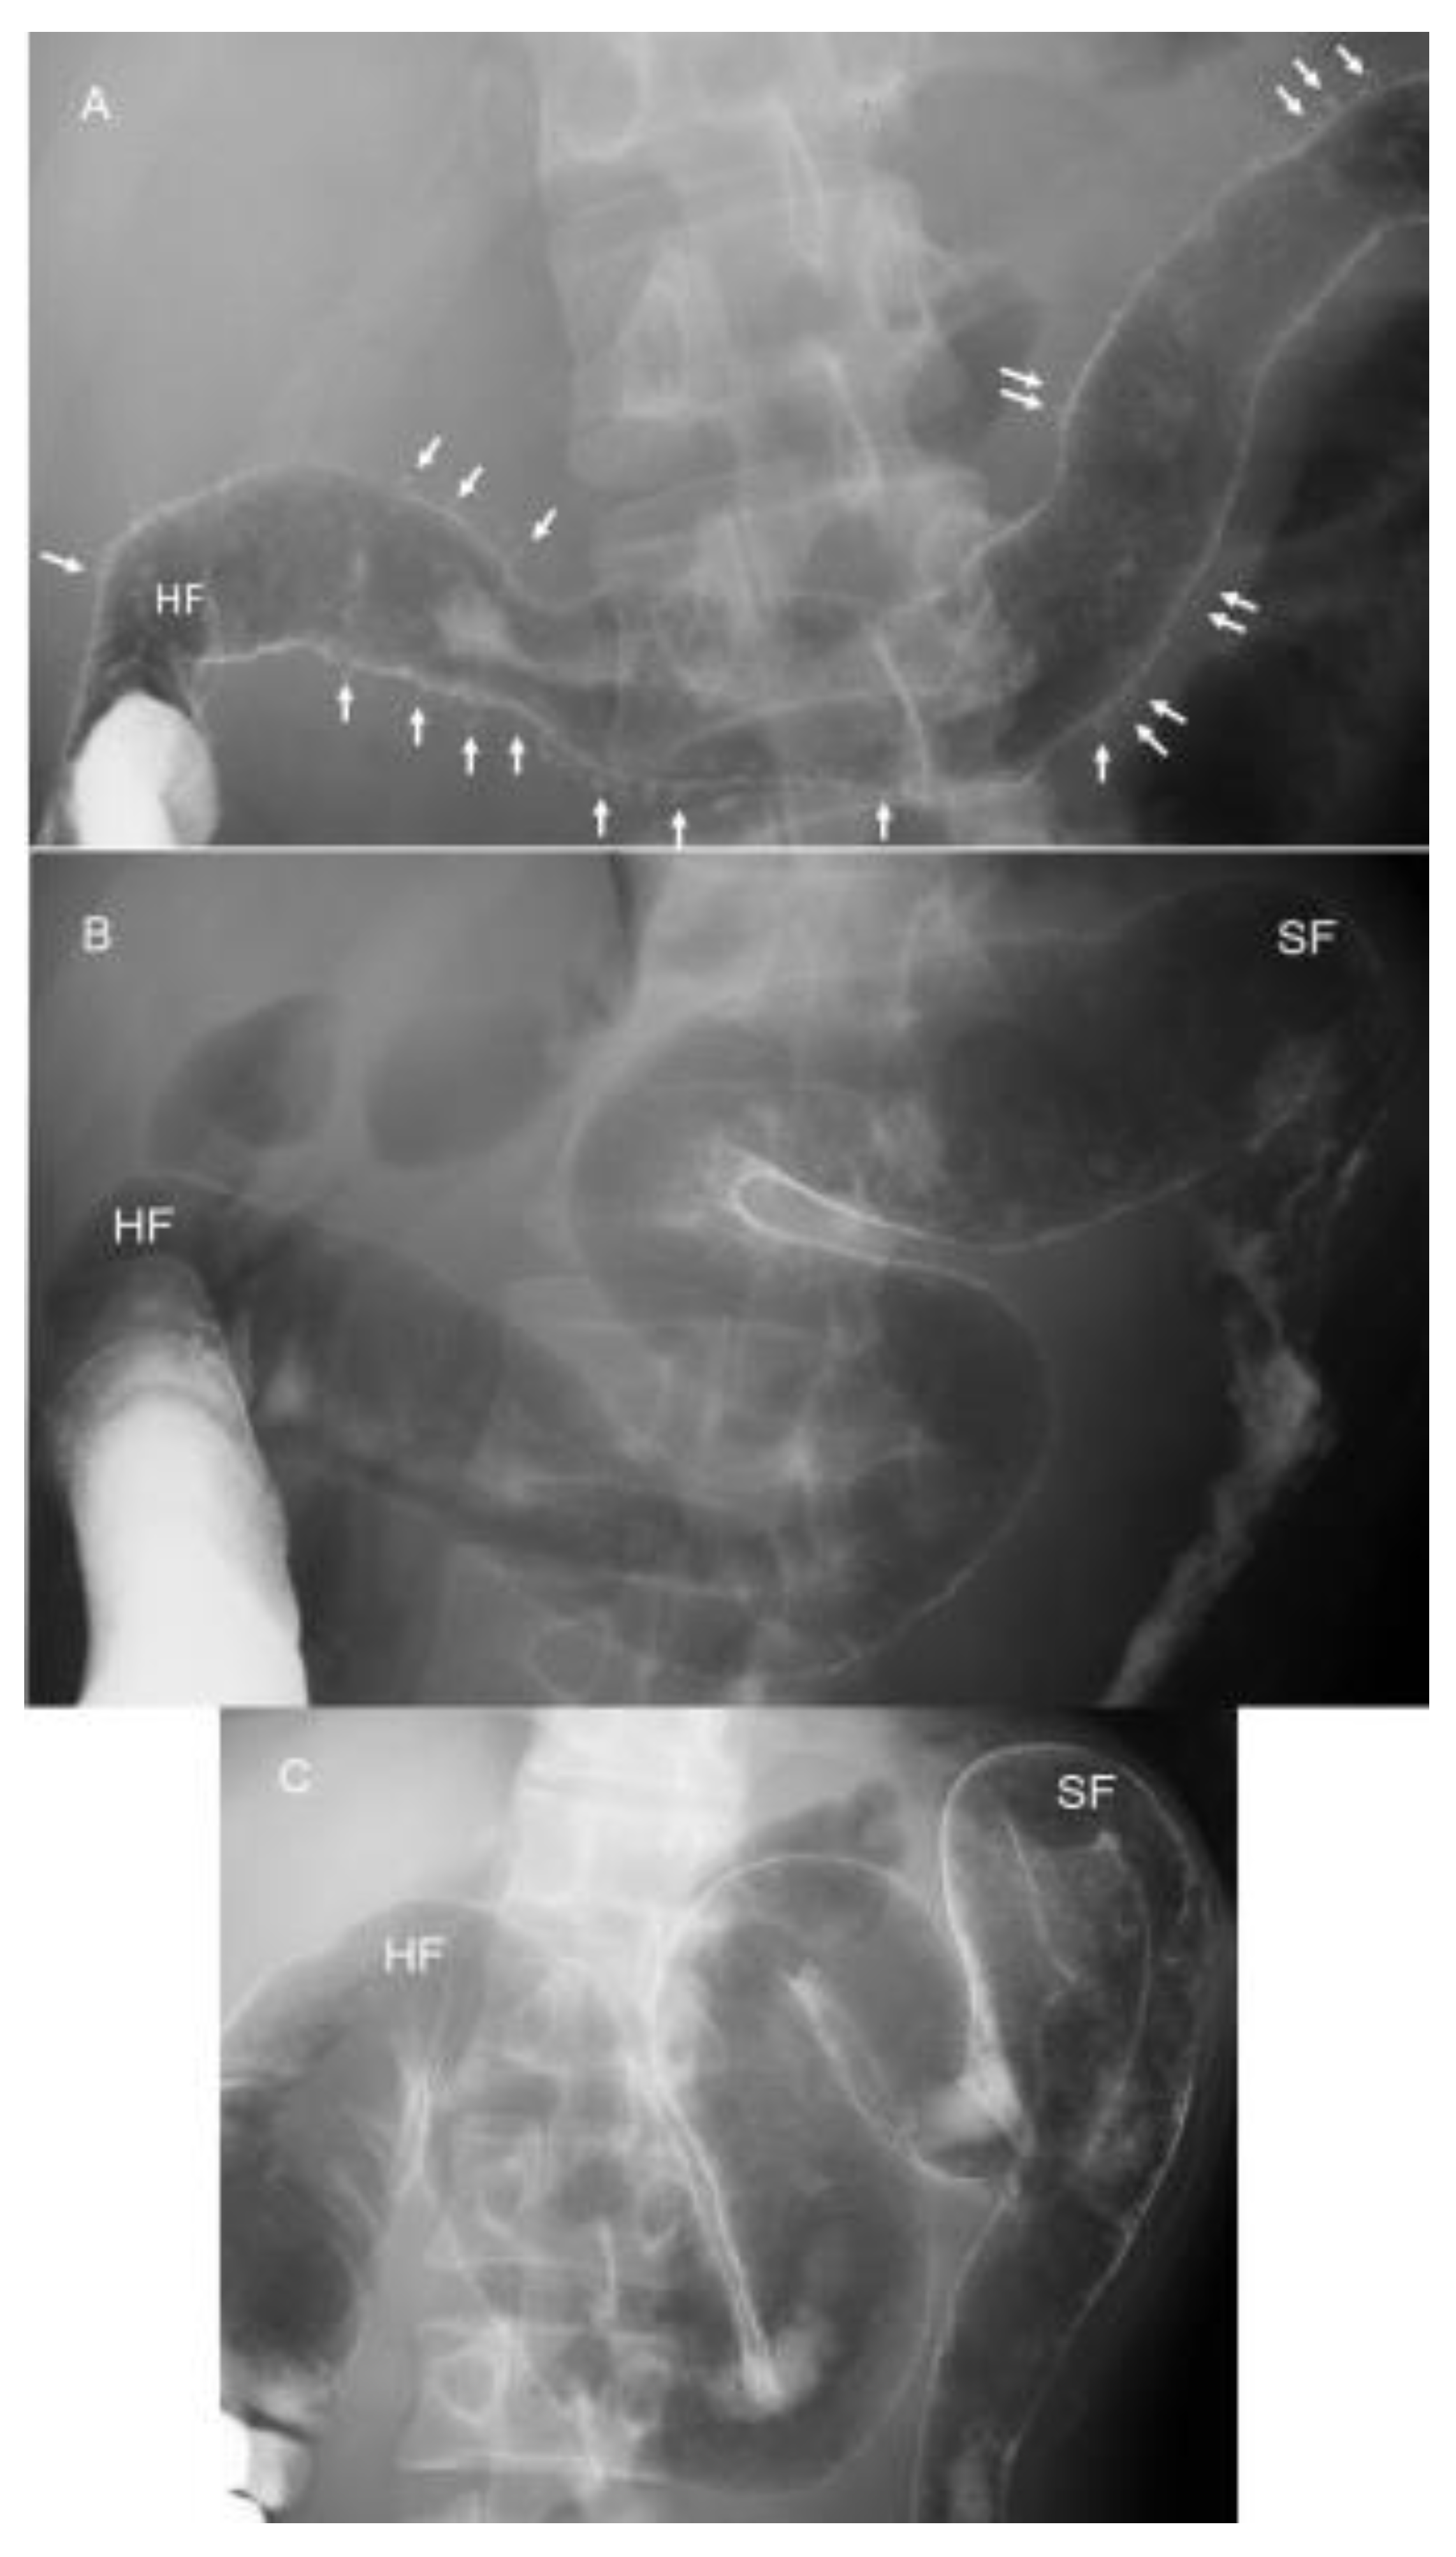

- Altaras, J. Radiologic features of inflammatory diseases of the colon. In Radiologic Atlas of the Colon and Rectum; Altaras, J., Ed.; Urban & Schwarzenberg Inc.: Baltimore, MD, USA, 1984; pp. 101–180. [Google Scholar]